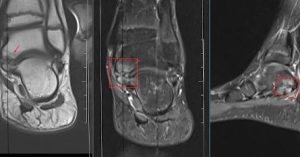

fibrous Talocalcaneal coalition

The medial talar process appears slightly prominent.

Marked subchondral bone marrow edema at medial aspect of subtalar joint involving the talus, calcaneal articular margins at the level of sustentaculum Tali associated with small effusion at the medial aspect –suggestive of fibrous Talocalcaneal coalitionfibrous Talocalcaneal coalition